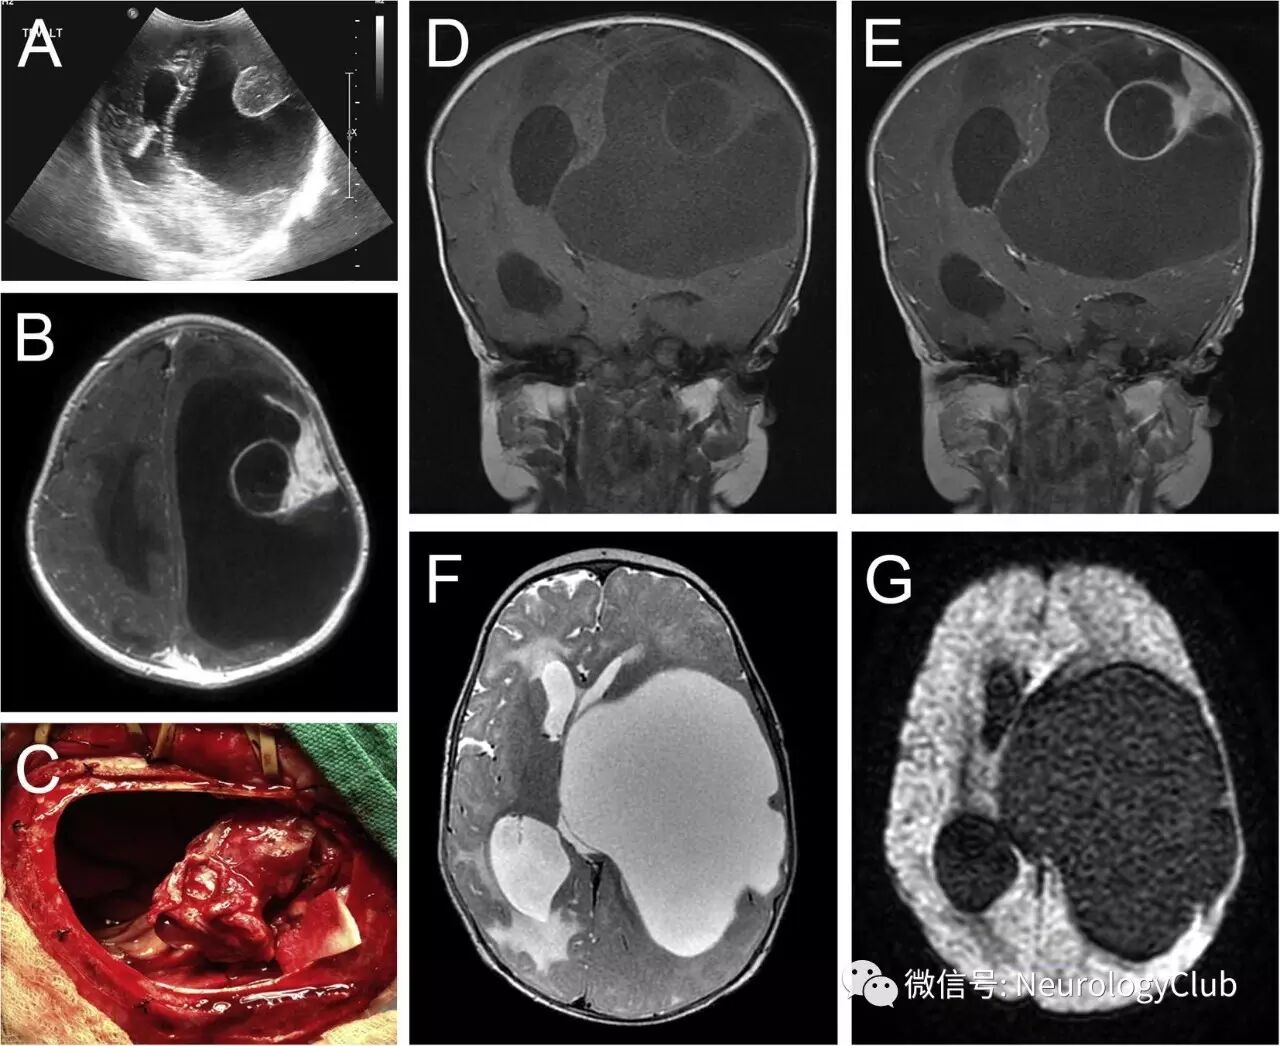

7月大男孩,表现为巨头畸形(头围52cm)。头颅轮廓检查可见明显扩张的头皮血管,前囟门抬高饱满,冠状缝和矢状缝轻微张开。患者保持右手呈握拳姿势,无法用右手去触及物体或脸;其右上肢明显肌张力亢进。颅神经和其他肢体查体正常。患儿既往史无殊。头颅超声提示左侧脑室显著扩大,伴圆形,边界清楚的高回声结构(图1A)。后行增强MRI检查(图1B,D-G)。

(图:A:超声证实左侧脑室明显扩张,伴边界清楚的高回声结节状病灶;B、E:增强T1WI;D:T1WI;F:T2WI;G:DWI;C:大囊肿术中引流所见;头颅MRI可见左侧大脑半球复杂的大囊,T2上与脑脊液等信号,DWI上未见弥散受限,增强时可见附着于硬脑膜的明显强化病灶,伴囊性成分)